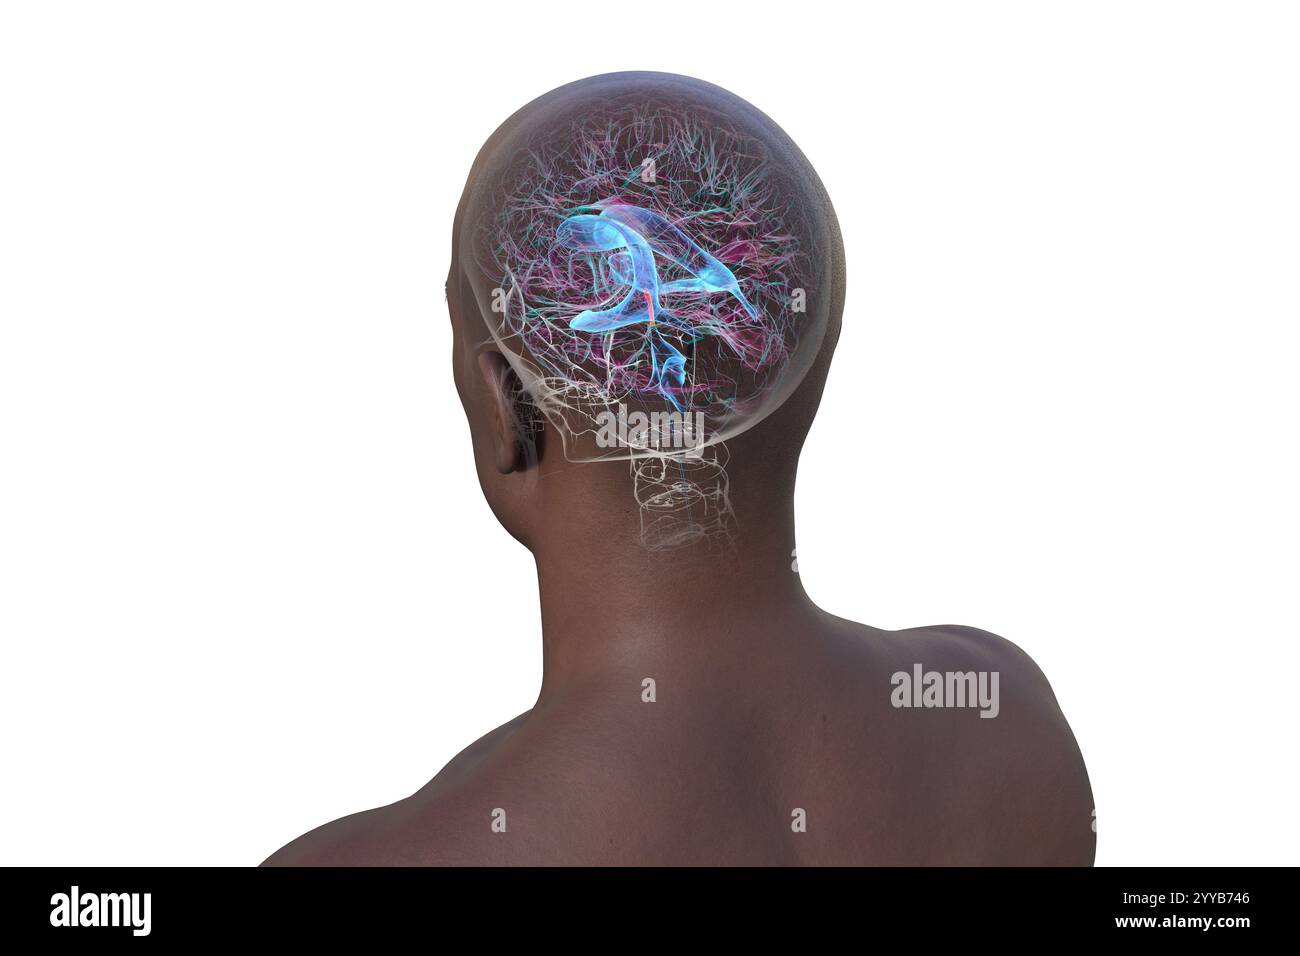

RF2YX6R0H–Computerdarstellung des menschlichen Gehirns mit orangefarbenem Aquädukt und grünem Ventrikelsystem, die den Liquorfluss (CSF) zeigen. Rückansicht.

RF2YYB740–Computerdarstellung des menschlichen Gehirns mit orangefarbenem Aquädukt und grünem Ventrikelsystem mit Liquorfluss. Rückansicht.

RF2YYB755–Computerdarstellung des cerebralen Aquädukts (orange), eines schmalen Kanals im Mittelhirn, der den dritten und vierten Ventrikel verbindet und den Liquorfluss erleichtert. Rückansicht.